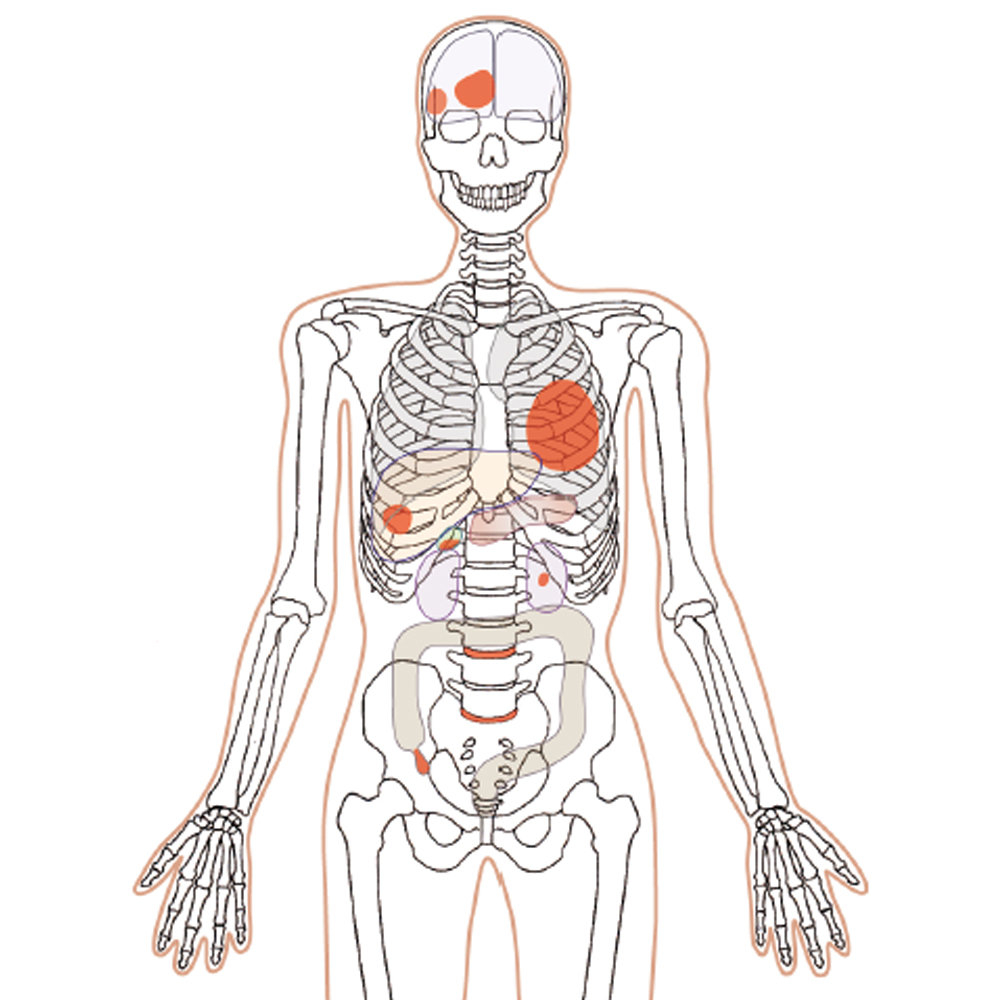

CT Whole Body Phantom - With Pathologies

1A unique, life size whole body phantom for CT provides a variety of educational application as well as visual evaluation in finding out optimal scanning conditions

| Case / Pathology | Refer to PDF( Anatomy and Pathologies) |